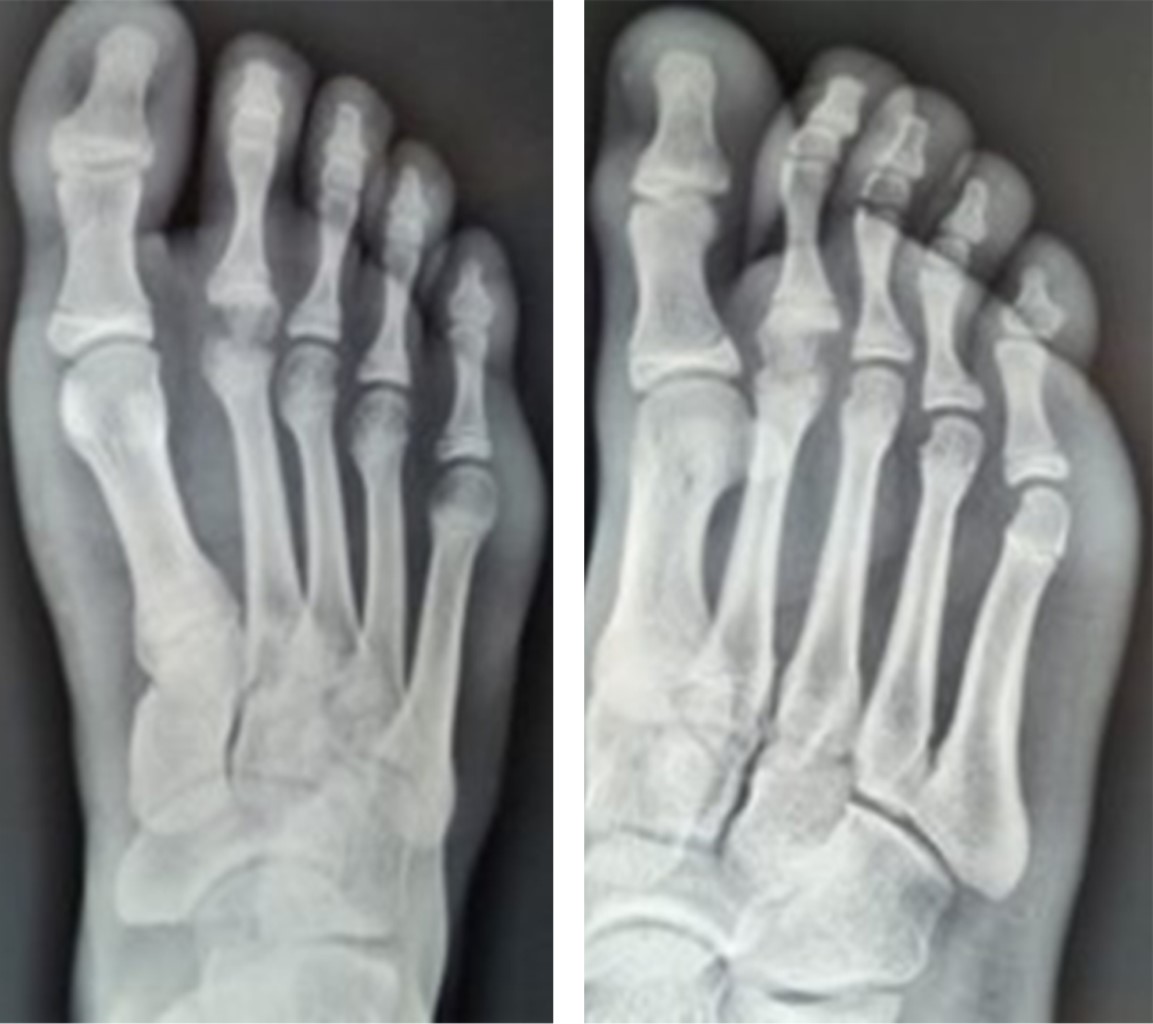

Con previo consentimiento de los padres y el paciente, se realiza reducción cerrada bajo anestesia local, se comprueba adecuada reducción con control radiológico (Figura 5). Se coloca zapato postquirúrgico y se inicia marcha a tolerancia. En seguimiento a corto, mediano y largo plazo sin evidencia de complicaciones; se anexan radiografías (Figura 6) a 30 meses de evolución.

Figura 6